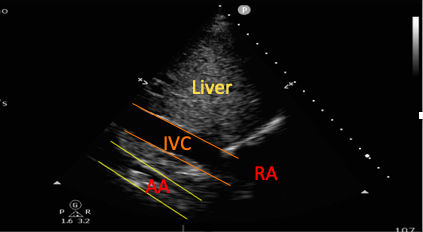

The Inferior Vena Cava

The IVC can be clearly visualized from the SC window both in longitudinal and transverse sections (Figure 4). The IVC diameter is measured at approximately 1-2 cm proximal to the right atrial junction, with a diameter >2 cm suggestive of IVC distension and potentially raised right atrial pressures.24 Dynamic assessment of the IVC can be performed by assessing the change in its diameter throughout the respiratory cycle.24 In mechanically ventilated patients, the IVC “distensibility index” with respiration can be used, with a dIVC ≥18% associated with 90% specificity and sensitivity for fluid responsiveness.15, 24

The Aorta

The abdominal aorta can be visualized in transverse and longitudinal axes from the SC window. This can aid with the diagnosis of pathologies such as aortic aneurysms or dissections (visualized as a flap within the vessel).25,26

Figure 4. Subcostal view showing both the inferior vena cava and the abdominal aorta (AA).

RA=right atrium